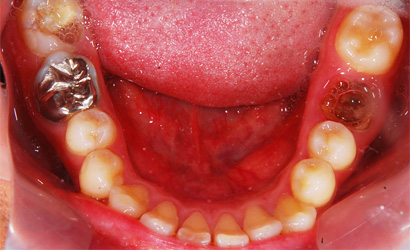

| 年齢・性別 | 20代・男性 |

|---|---|

| 主訴・治療部位 | 歯が痛い 下顎左側第一大臼歯 |

| 治療内容 | インプラント治療 |

| 治療費 | 保険外治療 約560,000円 |

| 治療期間 | 約半年 |

| リスク・副作用 | 外科処置により痛み、腫れを伴う |